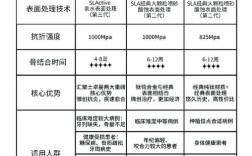

- 表面处理: 粗糙的表面处理有助于骨细胞附着,促进骨结合,可能对深度要求略有不同。